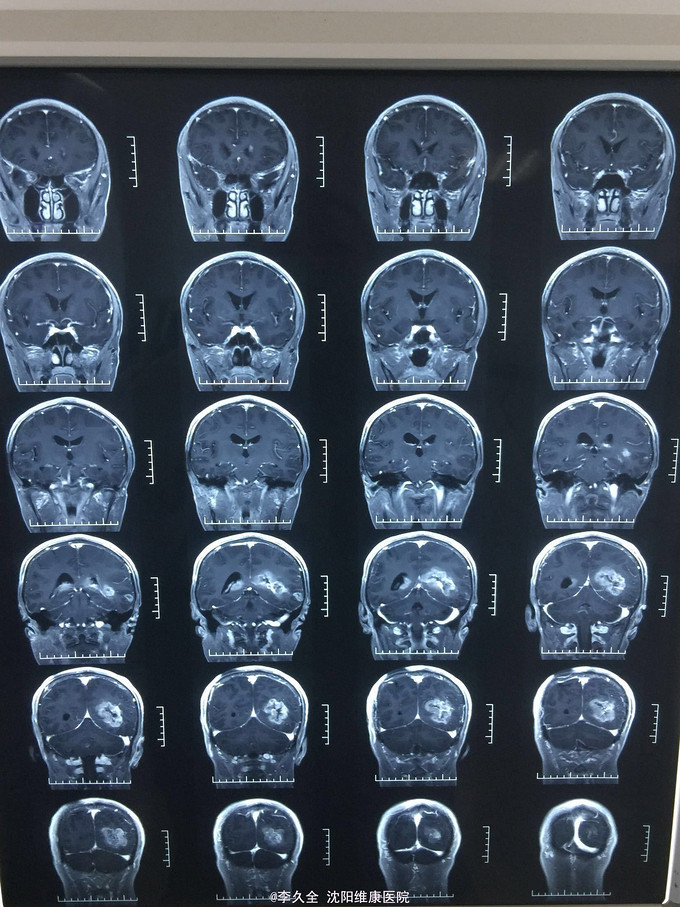

男,62岁,以头晕、视野缺损、记忆力减退、失写、失算7个月入院! 现病史:去年7月出现头晕,就诊于医院,行头CT:代诉未见异常,口服药物无效,后出现右侧视野缺损,走路撞墙、撞门,就诊于当地医院、北京协和医院,考虑“㬵质瘤”,近3个月出现近事遗忘为主,平时写字不会,计算力下降,不认识人! 既往史:2型糖尿病5年!

查体:BP:150/80mmHg,心肺腹无异常。神清,不能言语,失写、失算、失认,双曈孔等大正圆,直径3.0mm,光敏,四肢能够活动,右侧肌张力增高,巴氏征R+L-,颈强3横指,克氏征阳性! 影像MR:

1.颅内占位,胶母可能大! 2.2型糖尿病